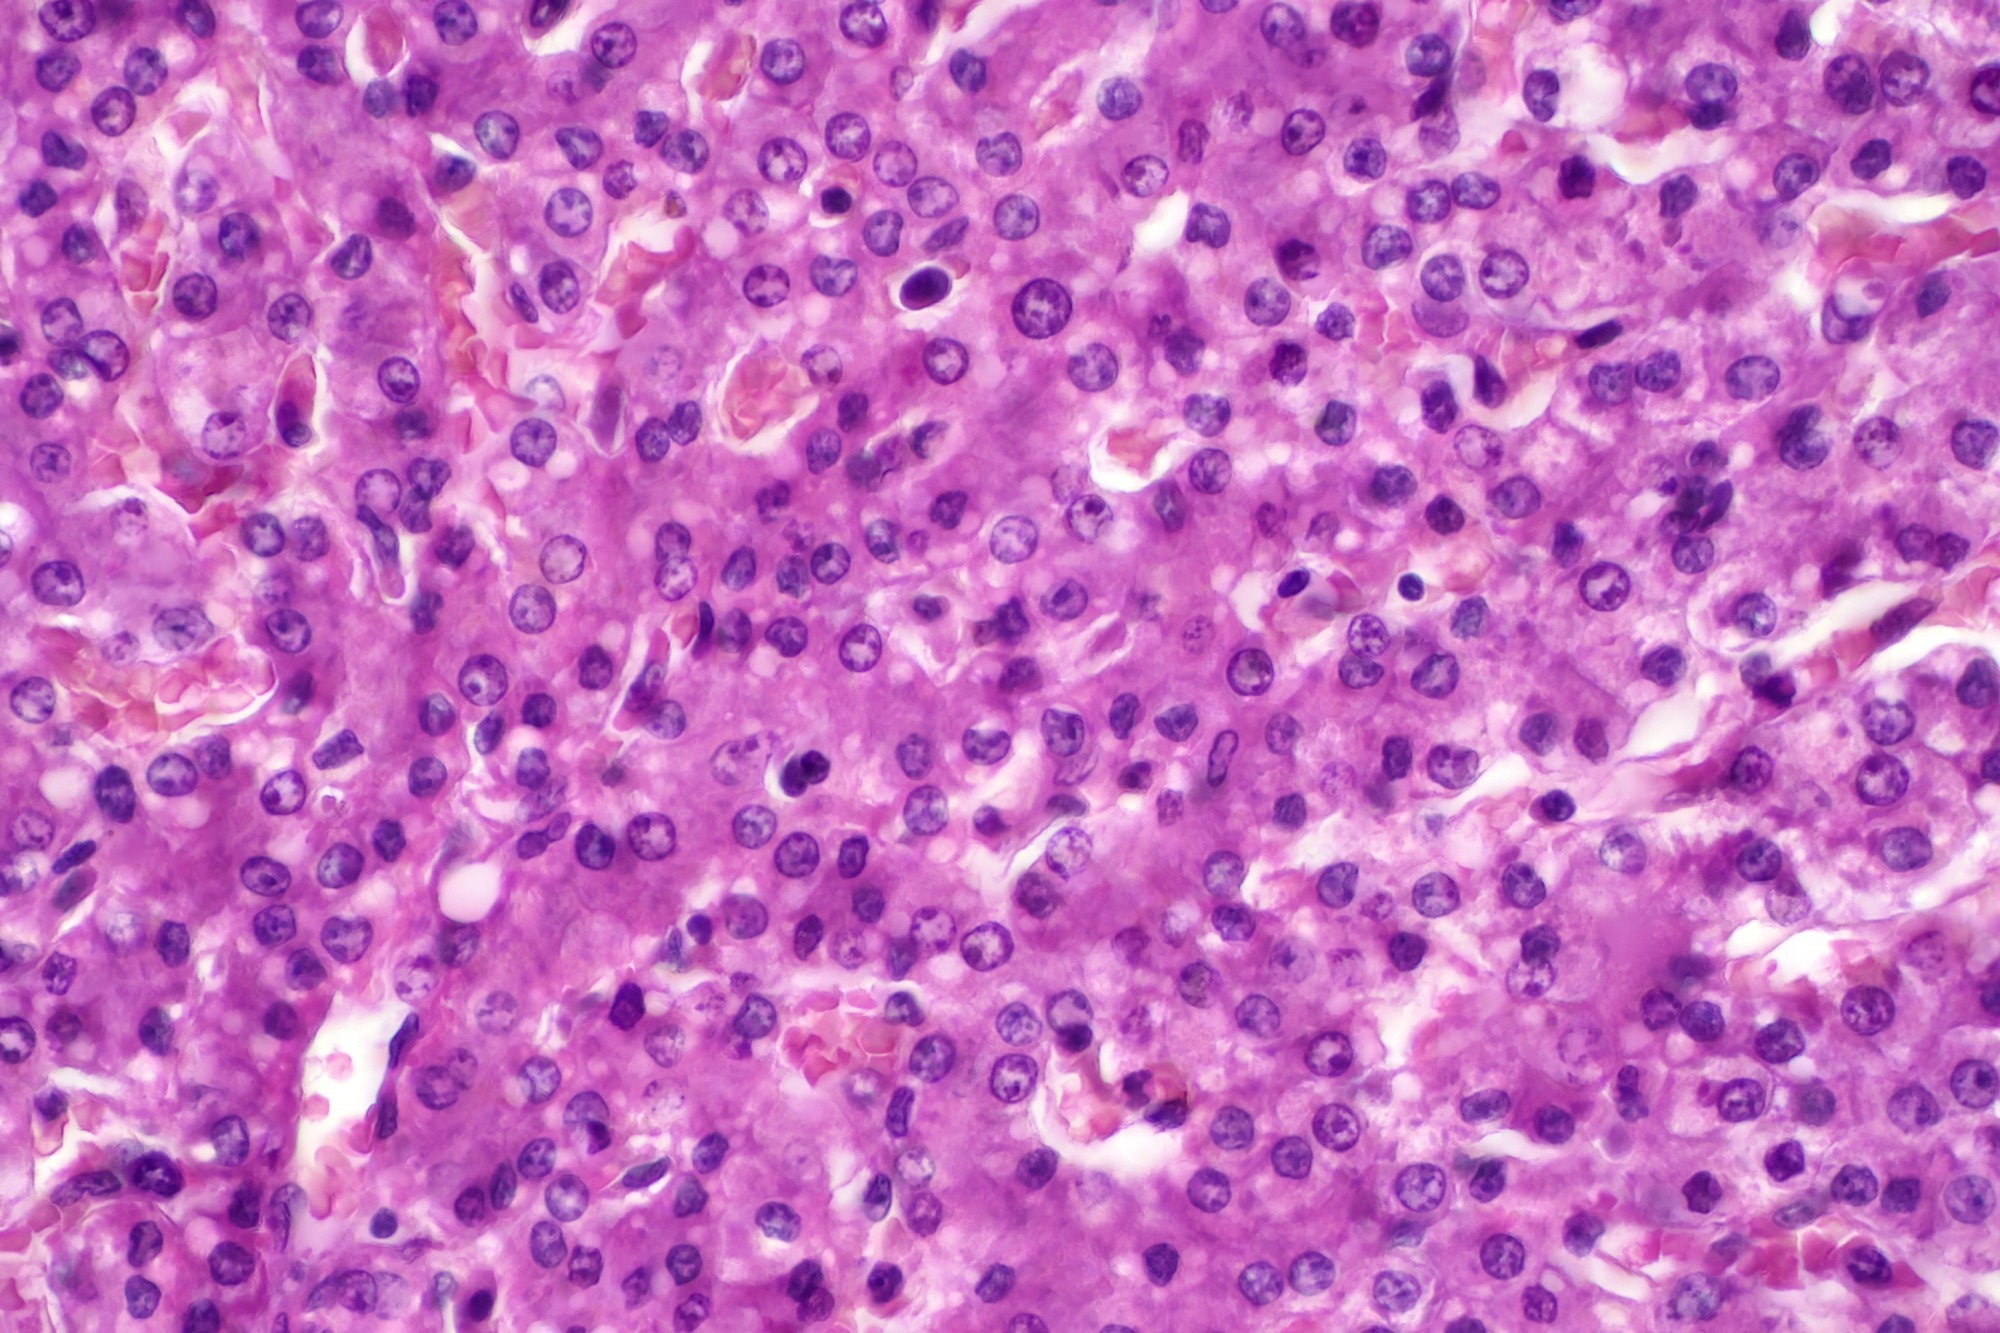

Image Credit: Choksawatdikorn/Shutterstock.com

Hepatocytes result image from the CellDrop FLi Automated Cell Counter.